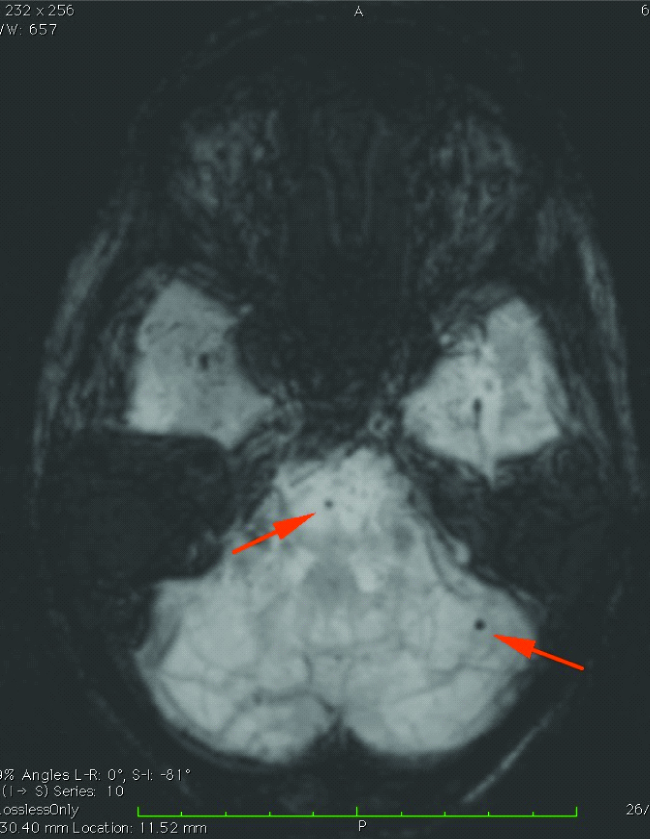

Brain MRI was performed on a 3T unit (Magnetom Spectra, Siemens). The following pulse sequences were used: - axial T2, FLAIR, sagittal T1, SWI, T2 coronal, diffusion imaging at B0, B1000 with ADC and 3D TOF MRA. MRI Brain SWI [Table/Fig-1] showed haemorrhages involving right cerebellum, pons, left posterior parietal lobe, both putamen and parietal sub cortical region with blooming of lesions in SWI representing microbleeds.

MIP SWI axial section of brain showing microbleeds in pons and left cerebellar hemisphere (represented by arrows).